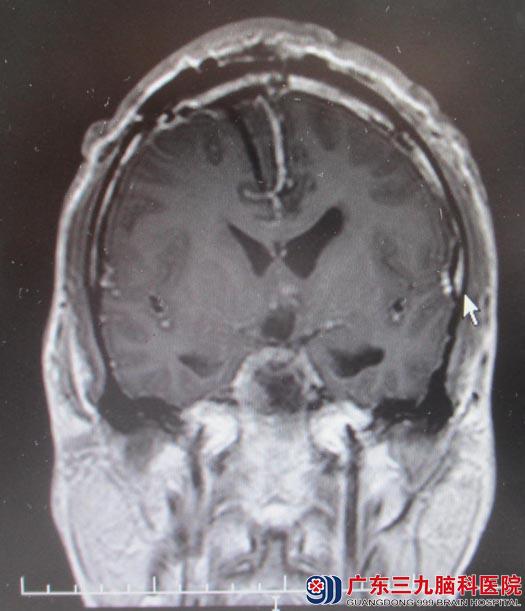

入住广东三九脑科医院综合神经外科,鲁明主任主刀急诊全麻下行经额胼胝体及前纵裂联合入路鞍区颅咽管瘤切除术。由于肿瘤为囊实性,从鞍区往三脑室方向生长,术中按经胼胝体入路作右侧额部弧形切口,铣刀取下4cm×5cm骨瓣,从纵裂逐步分离,切除肿瘤,90%的肿瘤组织顺利切除,但剩余10%的肿瘤与垂体柄粘连紧密,手术视野受限,为能全切肿瘤,术中果断延长手术切口,于右侧额部另铣一骨瓣,从前纵裂终板入路切除剩余肿瘤。最终肿瘤镜下全切,术后复查头颅MR未见肿瘤残留。术后小舟恢复良好,四肢活动正常,未出现异常并发症。

▲手术后